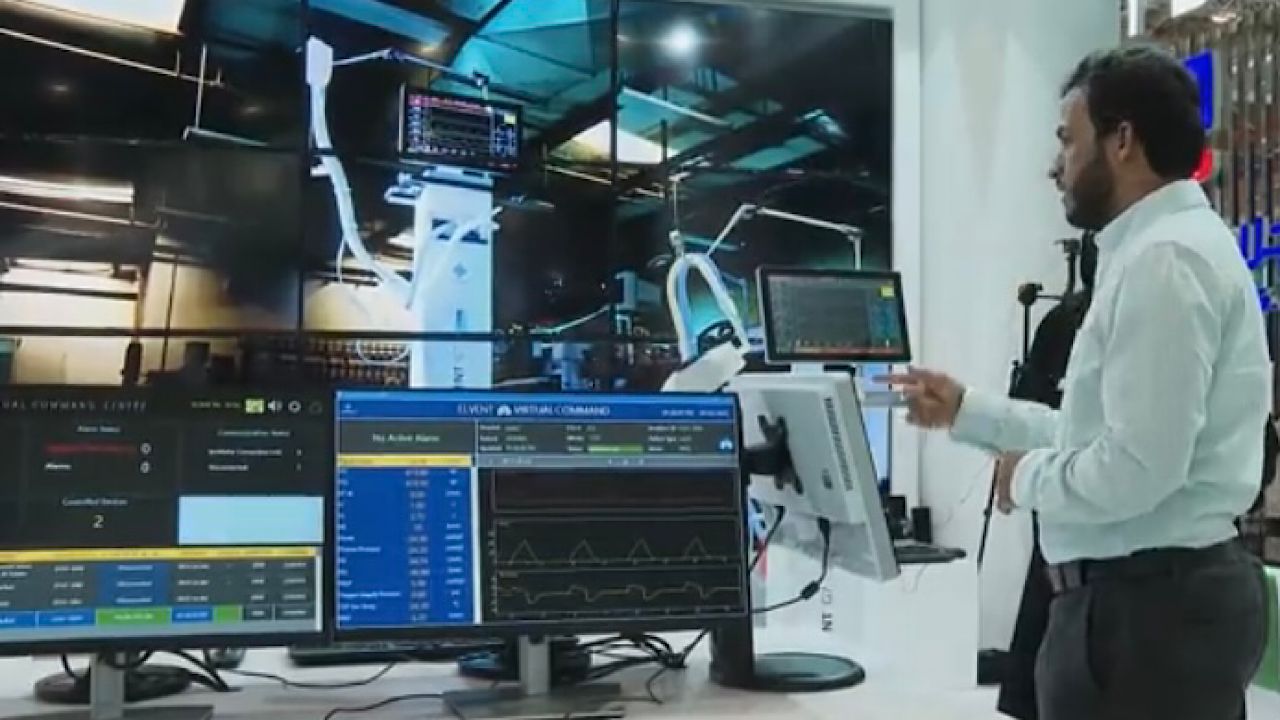

بالفيديو.. جهاز تنفس صناعي مبتكر محليًا بقدرات نوعية وتقنيات حديثة

منذ 2 سنة

0

1188